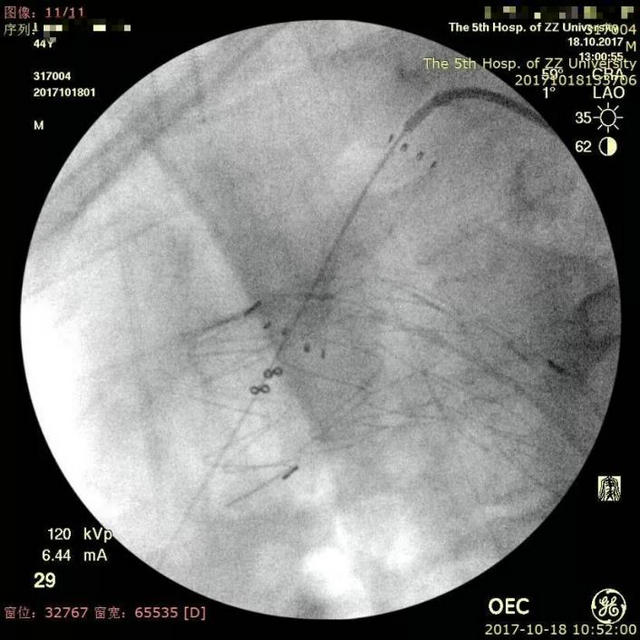

▲ 原位激光开窗

▲ 开窗后球囊扩张